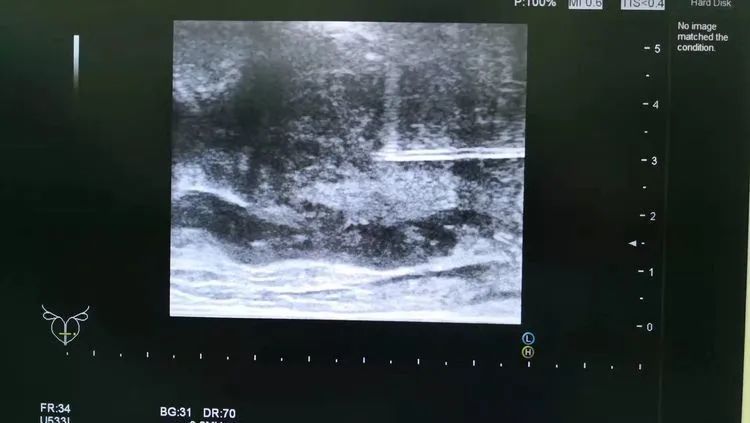

前列腺穿刺活檢是通過非常細的特制穿刺針(直徑1mm左右)獲取前列腺組織進行病理學檢查,是目前診斷前列腺癌最為有效的方法。

為更好的服務大衆,金年会体育引進了國際上先進的日立阿洛卡彩超機及經直腸雙平面超聲探頭,現已成熟開展彩超引導下經會陰前列腺穿刺活檢,與北京、上海、合肥等三甲大醫院成功接軌。

患者李先生,56歲,8月前發現PSA值輕度升高,先後在外院就診數次,均未明确診斷,建議随訪觀察。今年2月來到金年会体育總院泌尿外科行彩超引導下經會陰前列腺穿刺活檢,穿刺順利。術後病理提示為前列腺腺癌,Gleason評分3+4。後行前列腺癌根治性切除術,術後恢複佳,現已出院。